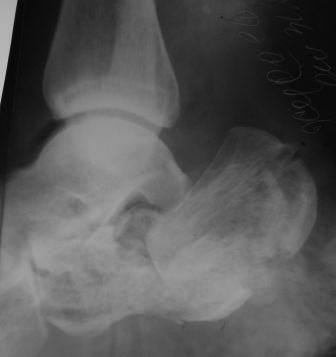

Постравматическая деформация пяточной кости

Уважаемые коллеги. Вчера госпитализирован пациент 1970г.р. , в ноябре 2014г, получил о/перелом пяточной кости. в другой клинике произведена КДО аппаратом Илизарова,

после трех месяцев аппарат сняли? , и больной начал наступать и ходить?- все это со слов б-ного(р-снимков нет.), Жалобы боли при ходьбе к-рая в динамике усиливается, об-но: деформация пяточной кости, движение в г/стоп.суставе почти в польном обьеме, по мед.поверхности пятки рубец плотно спаянный с костью.

Предварительный план: корригируюшая остеотомия пяточной кости, для создания свода стопы.( сможем ли опустить бугра пяточной кости из-за натяжения ахиллово сухожилия), и подтаранный артродез.